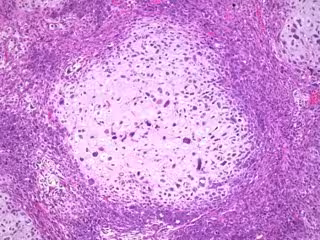

El cáncer de mama triple negativo es una forma de cáncer de mama agresiva y difícil de tratar porque las células cancerosas no tienen receptores para las hormonas, el estrógeno y la progesterona, ni la proteína HER2, lo que hace que muchos tratamientos sean ineficaces. Los investigadores han estado luchando por encontrar terapias dirigidas para el cáncer de mama triple negativo, por lo que el tratamiento principal sigue siendo la quimioterapia.